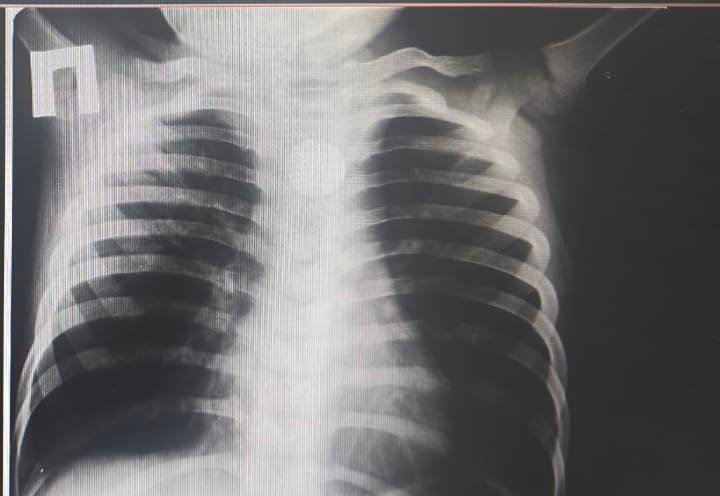

По словам матери малыша, после еды у ребёнка начался кашель, тошнота и обильное слюнотечение. При рентгенологическом исследовании в центральной районной больнице в пищеводе был обнаружен круглый металлический предмет – батарейка. Больного экстренно доставили на машине скорой помощи в Туркестанскую детскую областную больницу.

В отделении неотложной помощи хирурги и эндоскописты провели совместный осмотр и дополнительные исследования. Рентгенография подтвердила наличие инородного тела в верхней трети пищевода. Чтобы спасти жизнь ребёнка, хирурги немедленно провели операцию и успешно удалили инородное тело .